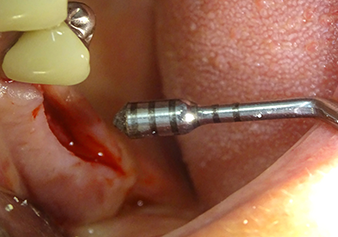

После промежуточного контроля (рис. 4) был проведен еще один этап подготовки (рис. 5). За тем, с помощью гидравлического инструмента Z35P мембрана была поднята в нужное положение (рис. 6 и 7). Далее, следовала дальнейшая пьезохирургическая подготовка ложа для имплантата, завершенная с помощью ротационного бора и лопаточной фрезы до диаметра имплантата 4,8 мм. Перед установкой имплантата под мембрану Шнейдера был введен аугментационный материал (размер частиц около 0,8-1,6 мм) (рис. 8).